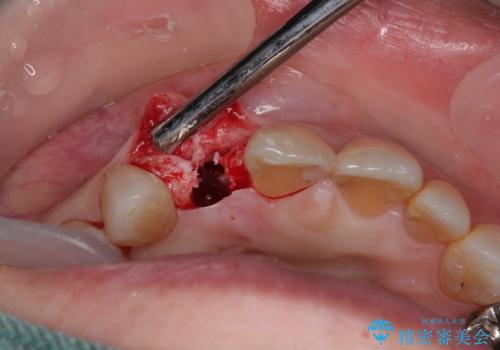

- 前歯のインプラント治療を検討して様々医院を探していたところ、1回の手術で治療ができるとのことで来院された患者様です。

長期間の治療と外科処置の回数が多くなることを懸念して、なかなかインプラント治療に乗り出せなかったそうですが、1DAYインプラントというものがあることを知り、当院にいらっしゃいました。

仮歯を事前に用意し、インプラント埋入時に即日で仮歯を装着する、即時荷重インプラントの計画で治療を進めて行くこととしました。